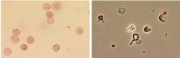

| תאריך | שם | תמונה ממוזערת | גודל | משתמש | תיאור | גרסאות |

|---|---|---|---|---|---|---|

| 05:57, 27 באוגוסט 2012 | שתן14.jpg (קובץ) | 102 קילו־בייטים | Nachi | 2 | ||

| 05:56, 27 באוגוסט 2012 | שתן13.jpg (קובץ) |  |

84 קילו־בייטים | Nachi | 2 | |

| 05:55, 27 באוגוסט 2012 | שתן12.jpg (קובץ) |  |

77 קילו־בייטים | Nachi | 2 | |

| 05:54, 27 באוגוסט 2012 | שתן11.jpg (קובץ) |  |

107 קילו־בייטים | Nachi | 2 | |

| 05:54, 27 באוגוסט 2012 | שתן10.jpg (קובץ) |  |

125 קילו־בייטים | Nachi | 2 | |

| 05:53, 27 באוגוסט 2012 | שתן9.jpg (קובץ) |  |

113 קילו־בייטים | Nachi | 2 | |

| 05:52, 27 באוגוסט 2012 | שתן8.jpg (קובץ) |  |

70 קילו־בייטים | Nachi | 2 | |

| 05:52, 27 באוגוסט 2012 | שתן7.jpg (קובץ) |  |

91 קילו־בייטים | Nachi | 2 | |

| 05:51, 27 באוגוסט 2012 | שתן6.jpg (קובץ) |  |

66 קילו־בייטים | Nachi | 2 | |

| 05:50, 27 באוגוסט 2012 | שתן5.jpg (קובץ) |  |

49 קילו־בייטים | Nachi | 2 | |

| 05:49, 27 באוגוסט 2012 | שתן4.jpg (קובץ) | 102 קילו־בייטים | Nachi | 2 | ||

| 05:49, 27 באוגוסט 2012 | שתן3.jpg (קובץ) |  |

67 קילו־בייטים | Nachi | 3 | |

| 05:47, 27 באוגוסט 2012 | שתן2.jpg (קובץ) |  |

43 קילו־בייטים | Nachi | 3 | |

| 05:46, 27 באוגוסט 2012 | שתן1.jpg (קובץ) |  |

106 קילו־בייטים | Nachi | 2 | |